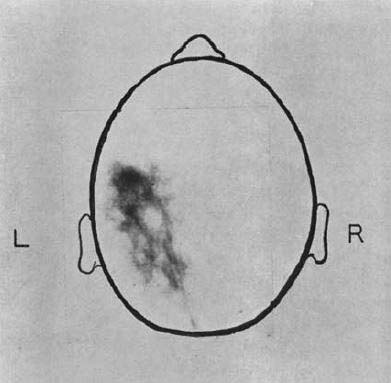

図10. PET-CT(2000年).肺癌とその縦隔転移(→)[40].

核医学画像の欠点のひとつに,解剖学的な局在情報の取得が難しいことが挙げられる.早くも1966年に,Kuhlらはtranmission scanと emission scanを同時に撮影する方法を提唱しているが,実用にはいたらなかった[36].この問題を根本的に解決したのが Geneva大学のDavid Townsend,Tennessee大学のRonald Nuttが1990年代に開発した,PETとCTを1台の装置に組込んで患者を移動することなく連続して撮影,画像を合成するPET-CTであった[37](図10).1998年にPittsburgh大学でプロトタイプが稼働し,特にFDGによる腫瘍診断における有用性が高く評価され,2001年にGE社(Discovery LS),次いでSiemens社(Biograph)により製品化された*.PET-CTは以後急速に普及し,2006年には単独PET装置は姿を消した[35].